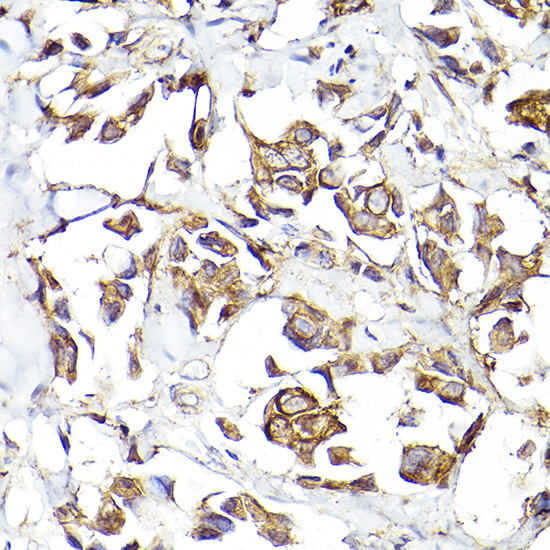

Immunohistochemistry of paraffin-embedded human breast cancer using Fibroblast activation protein-?? (FAP) Rabbit pAb.